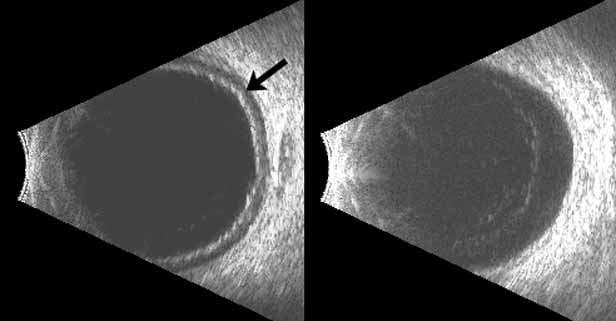

Both benign and malignant tumors can produce a secondary glaucoma. Shields and associates29 found 5% (126) of 2,704 eyes diagnosed with intraocular tumors suffered glaucoma. The glaucoma rate was only 2% in eyes with choroidal melanomas but rose to 17% in eyes with melanomas of the ciliary body.28 The mechanism of glaucoma in posterior segment melanomas was usually iris neovascularization (Fig. 4; Table 3).30 The incidence of glaucoma in tumor-containing eyes was found to rise when retinal detachment was present. In eyes presenting with reduced vision, glaucoma, opaque media, and an uncertain history of visual loss, it is prudent to exclude an unsuspected neoplasm by performing diagnostic B-scan ultrasonography.

Melanomalytic glaucoma is the term applied to glaucoma due to macrophages laden with pigment released from necrosis of a ciliary body melanoma.31 However, because a similar picture may occur with a nonmalignant tumor (melanocytoma), the presence of glaucoma associated with a pigmented mass does not itself confirm the diagnosis of malignancy. Posterior segment metastases caused a pressure elevation due to angle closure–related choroidal mass effect or retinal detachment in only 1% of eyes.29